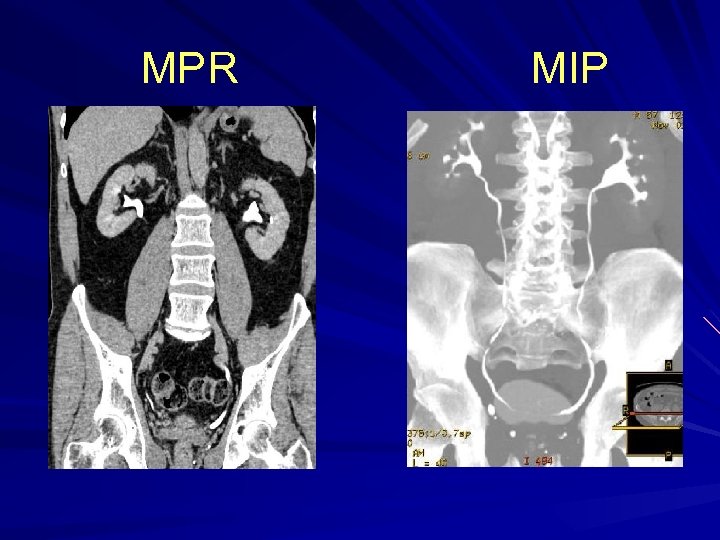

Axial images – Normal CTU

MPR MIP